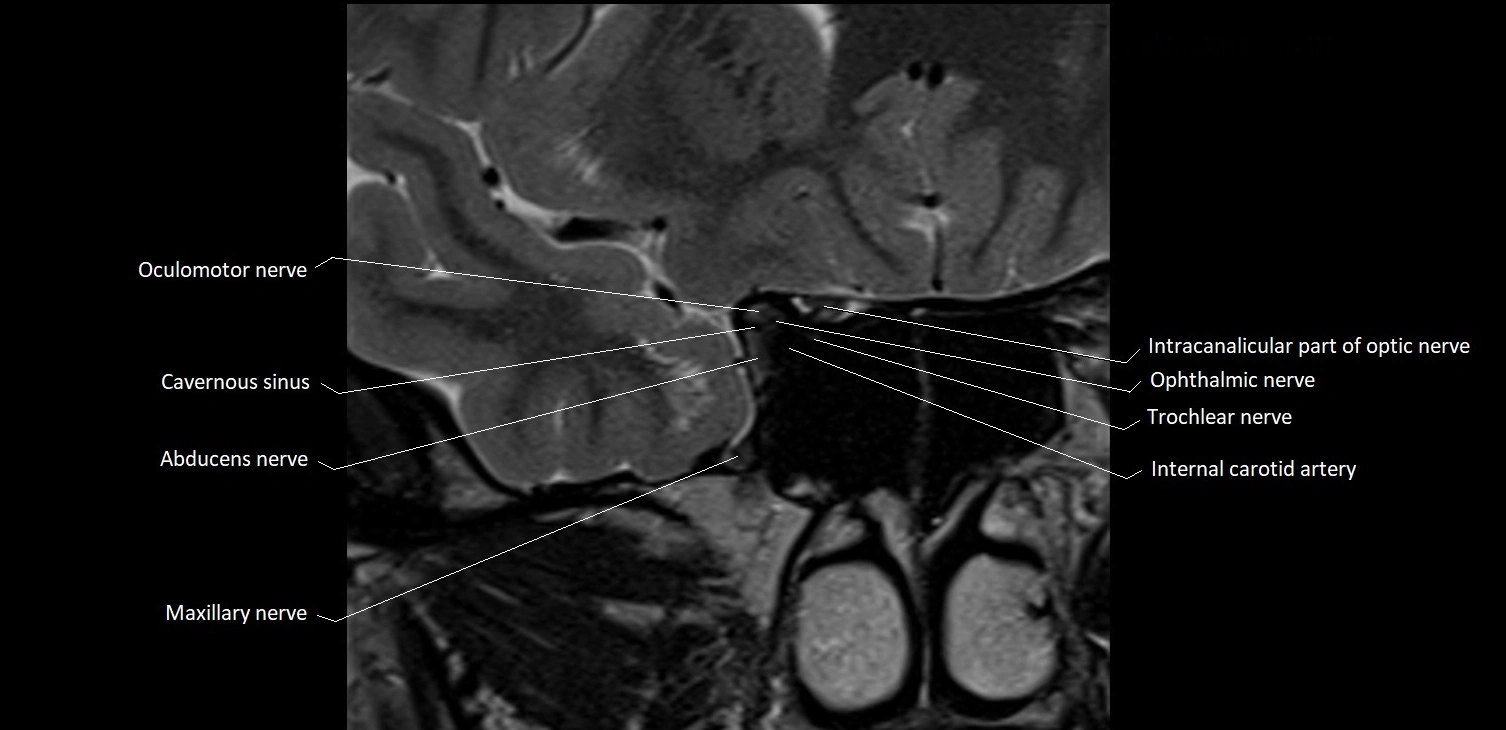

- Abducens nerve (Cranial nerve VI)

- Trochlear nerve (Cranial nerve IV)

- Oculomotor Nerve (Cranial Nerve III)

- Maxillary nerve

- Intracanalicular part of optic nerve